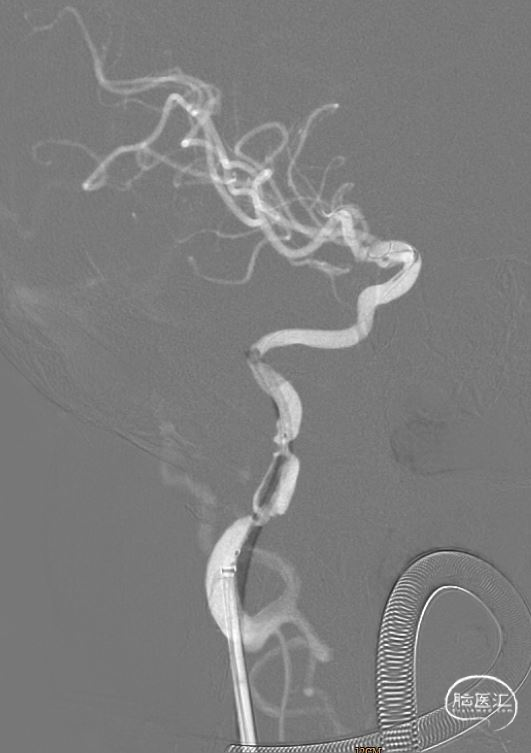

沿微导管送入取栓支架(6mm*30mm),准确对位后成功释放,撤出微导管,造影提示右侧颈内动脉及右侧大脑中动脉有前向血流,等待5分钟后,跟进颅内支持导管至颈内动脉C2段,缓慢回撤取栓支架,并沿中间导管抽吸,可见支架缠绕少量血栓,送入Synchro-2 微导丝3m至C7段,回撤中间导管,再次造影提示右侧颈内动脉C1段重度狭窄伴夹层样改变,观察10分钟血流较前减慢。

撤除中间导管,沿微导丝送入Viatrac 14球囊(4*30mm),在球囊的引导下,将6F 长鞘送至颈动脉C2段远端,撤出球囊。

球囊输送系统带6F 长鞘通过病变(特洛伊木马技术),撤出球囊后,6F 长鞘带Xpert Pro支架输送系统通过病变 。

再次沿导丝送入Xpert Pro(6X40mm)支架,回撤长鞘,对位准确后成功释放支架,再次造影提示支架贴壁良好,前向血流通畅(TICI分级3级)。

观察十分钟后再次造影提示右侧颈内动脉全程血流通畅,无明显急性血管闭塞征象,前向血流3级。术中DynaCT未见明显造影剂渗出。撤出导引导管,拔除动脉鞘,使用雅培缝合器 ProGlide缝合伤口,伤口加压包扎,结束手术。